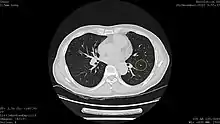

![]() Computed tomography (CT) scanner, the usually recommended screening technique | |

Results from large randomized studies have recently prompted a large number of professional organizations and governmental agencies in the U.S. to now recommend lung cancer screening in select populations. The 3 main types of lung cancer screening are low-dose, computerized tomographic (LDCT) screening, chest x-rays, and sputum cytology tests.[4] Currently multiple professional organizations, as well as the United States Preventive Services Task Force (USPSTF), the Centers for Medicare and Medicaid Services (CMS) and the European Commission's science advisors[5] concur and endorse low-dose, computerized tomographic screening for individuals at high-risk of lung cancer.